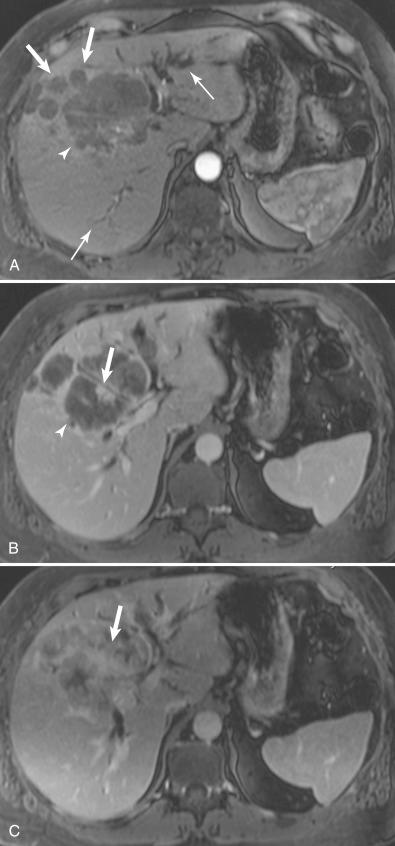

Figure 4.3, Cholangiocarcinoma. A 48-year-old female with jaundice shows an irregular mass. A , On the arterial phase of magnetic resonance imaging, the mass ( arrowhead ) shows minimal peripheral enhancement. Satellite nodules are seen ( thick arrows ). There is bilobar biliary dilation ( thin arrow ). B , On the venous phase, the mass ( arrowhead ) shows more enhancement ( thick arrow ). C , On the 5-minute delayed phase, there is gradual centripetal enhancement ( thick arrow ). The slow progressive inhomogeneous enhancement is typical of cholangiocarcinoma.